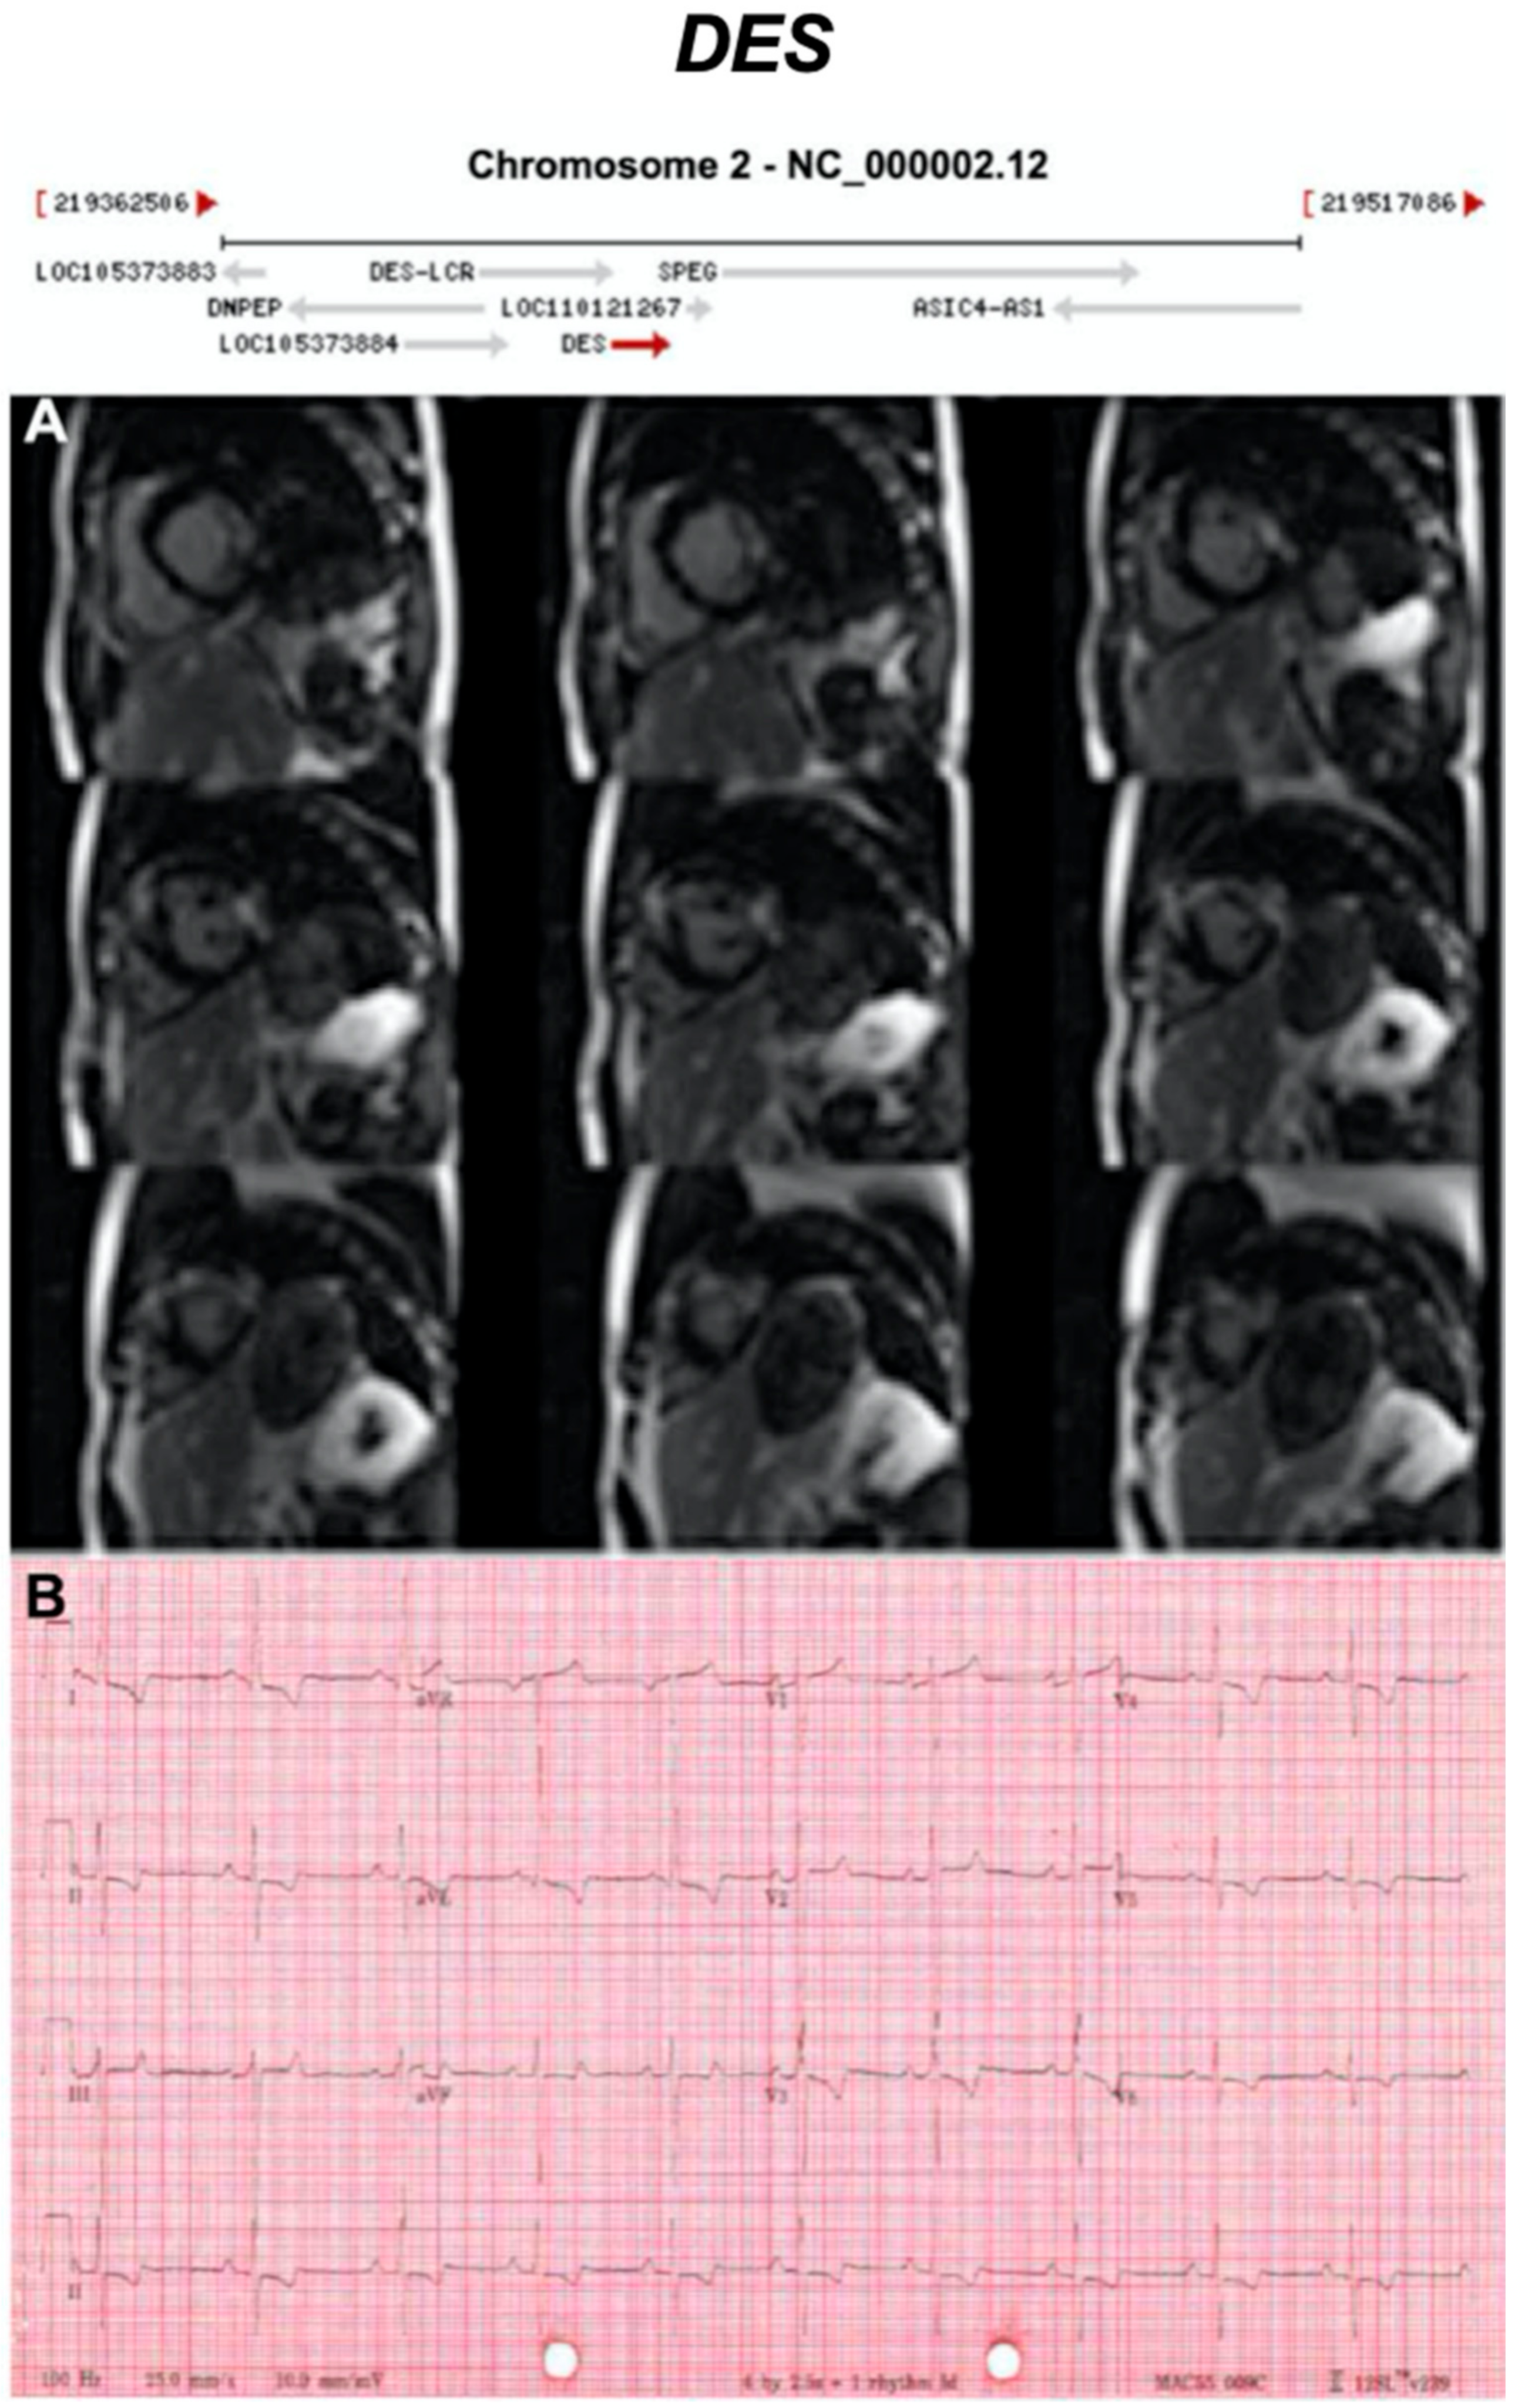

Figure 11.

Exemplar MRI and ECG finding found in ACM patients with DES mutations. (A) CMR of a patient with DES mutation (deletion of guanine at position 735) showing extensive mid-wall fibrosis (LGE short-axis view); (B) 12-lead ECG of a different patient with p.Gly382Val mutation of the LMNA gene showing sinus tachycardia, inverted T waves in V1–V3 ad poor R wave progression. Reproduced from Koitka et al. (2017) with permission [42].